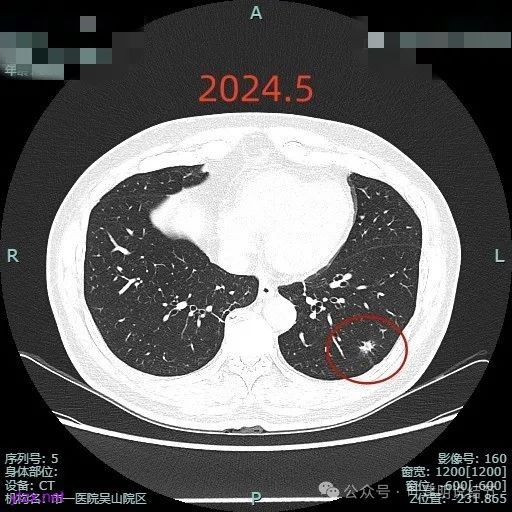

下面是2024年5月复查时的靶重建影像与我的意见:

病灶毛刺空泡(或细支气管扩张)都有,表面不平,灶内杂乱。

但纵向看是偏条状些的,密度较高,边上有少许磨玻璃成分,磨玻璃部分略显模糊。

中间实性部分密度过高,边上的的毛刺显得过长,且不太锐利。

实性成分密度较高,边上有淡磨玻璃成分,毛刺明显。

密度高,边上磨玻璃成分淡,表面不平,毛刺不太锐利,整体感觉缺乏收缩力。

相应支气管有扩张,边上的磨玻璃成分偏糊,界限欠清。

进入的血管没有异常增粗,棘突不太锐利,磨玻璃成分偏糊。

上图倒是血管显得有点异常增粗的,总体膨胀性不强,收缩力不够。

我的意见是纵向看线状,考虑慢性炎伴纤维增生可能性大些,建议4-6个月复查。